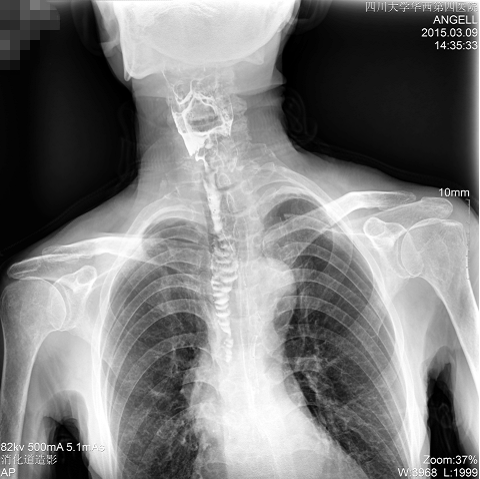

图为斜位:通过动态影像可以清楚看到钡剂进入了支气管道

通过多功能dr可以诊断该病人的症状为会厌功能紊乱,钡剂进入到了气管。而在动态透视下可以清晰的观察到钡剂从何处进入气管,可清晰显示食管粘膜结构。使用多功能dr其独特的视频采集技术,可实时保存视频并能实现900万像素实时点片,才能获取这样清晰的病灶点。而常规dr只能拍摄静态片,且成像效果大打折扣,因此较难确诊病灶。